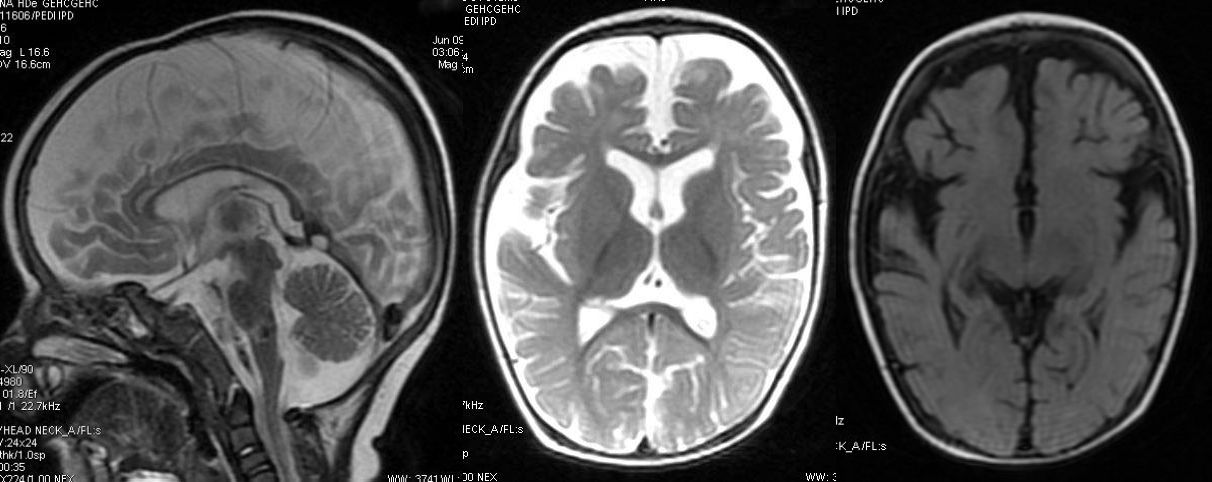

T2W axial, sagittal and axial FLAIR sequence revealing significant atrophy predominantly involving the frontal and temporal lobes and reduced volume of corpus callosum. Also, noted marginally poor myelination, predominantly peritrigonal white matter.

Non specific cerebral atrophy of different grades was observed in all cases except one. In [Table/Fig-2], reduced thickness of corpus callosum was observed in six patients on MRI brain studies. ITS cases who had severe wasting, three out of four showed evidence of cerebral atrophy; all three children with moderate wasting had evidence of cerebral atrophy. Cerebral atrophy was observed in all children with stunting as well as in children having normal height for age and sex. Some patients (6/10) had mild to moderate ventricular dilatation and most patients (9/10) had prominence of Sylvian sulcus. Ventricular dilatation and prominence of Sylvian sulcus had correlation with the grades of cerebral atrophy in all cases [Table/Fig-3,4,5,6,7,8,9,10,11 and 12].

In Ramakumar L et al., study, an unusual finding was observed, 4 out of 29 of the nerve biopsies revealed partial demyelination and swelling of the myelin sheath in ITS cases [25]. One study revealed that early cerebellar atrophy is indicated by homogeneity of the white matter signal; and lesions in deep white matter on T2-weighted images, other changes in hypomyelinating disorders included abnormal signal intensity in basal ganglia and pons [12].